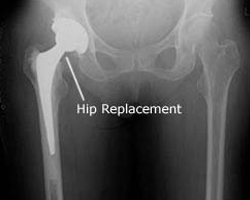

During a hip replacement operation, the surgeon removes damaged cartilage and bone from your hip joint and replaces them with new , man-made parts.

The hip joint is made up of the interconnection of two bones in a ball and socket:

1) the socket in the pelvis (acetabulum), 2) the ball (femoral head). Hip fractures refer to the femur fracture.

Almost all hip fractures require surgery and the type of surgery depends upon where in the femur that the fracture is located.